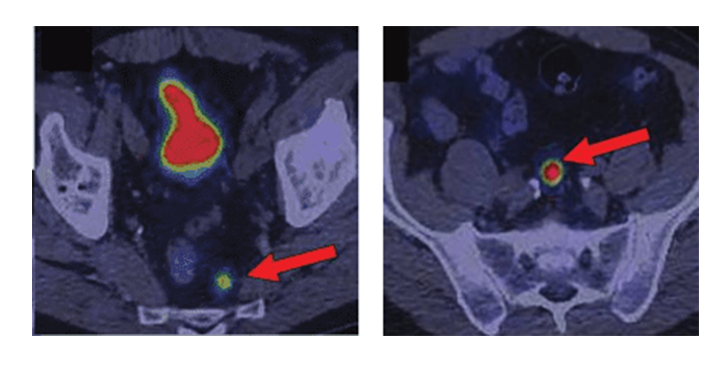

Рисунок 4. Накопление радиофармпрепарата 68Ga-DOTA-TATE пораженными лимфатическими узлами у пациента с НЭО прямой кишки.